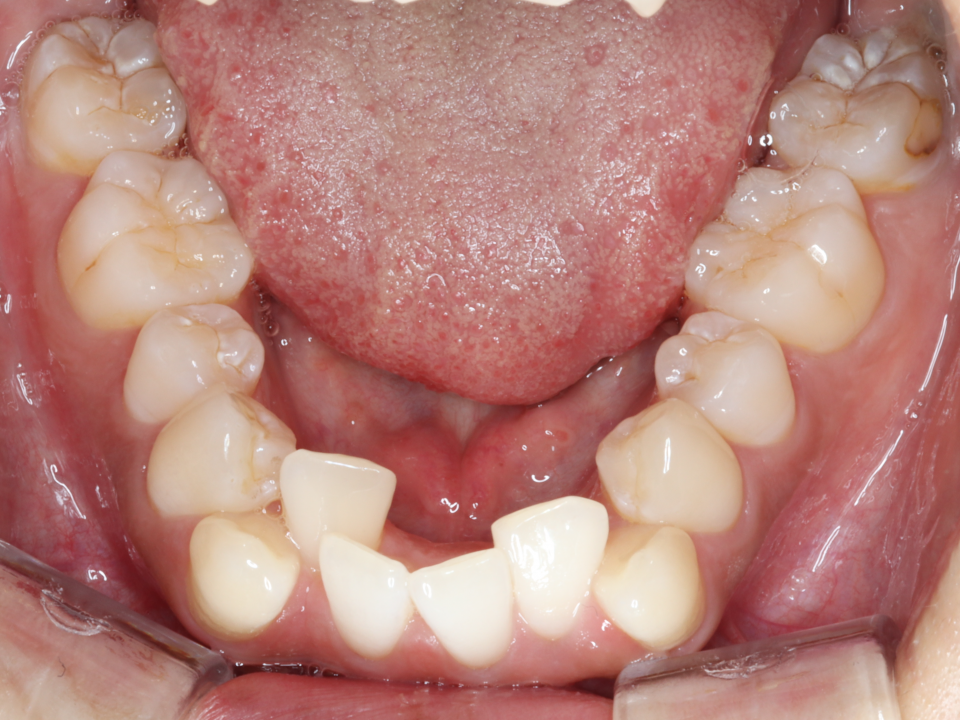

20代女性 下顎前突・叢生をワイヤーで治療

Before

治療テーマ 下顎前突・叢生をワイヤーで治療(4⏊4・4⏉4と過剰歯を抜歯)

患者様の年齢/性別 20代女性

矯正治療期間 1年10か月

治療費用 982,000(税込み)